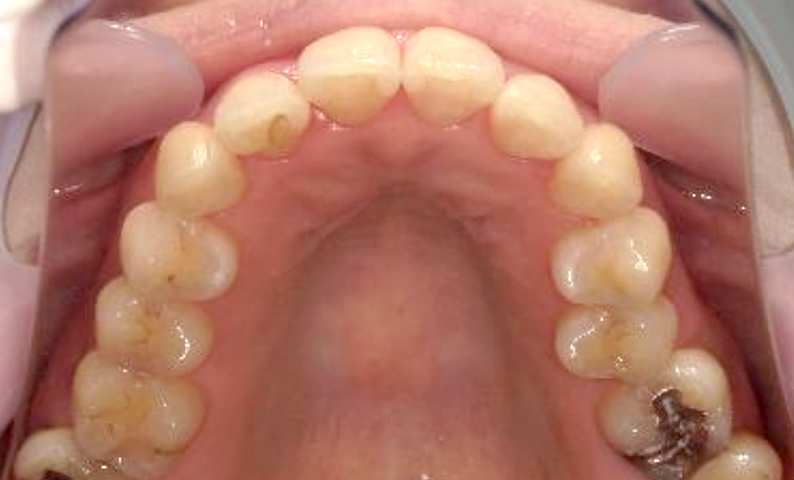

症例_003 上下顎の部分矯正

治療期間:12ヶ月金額:54万円+税男性八重歯前歯のガタガタ

| Before | After |